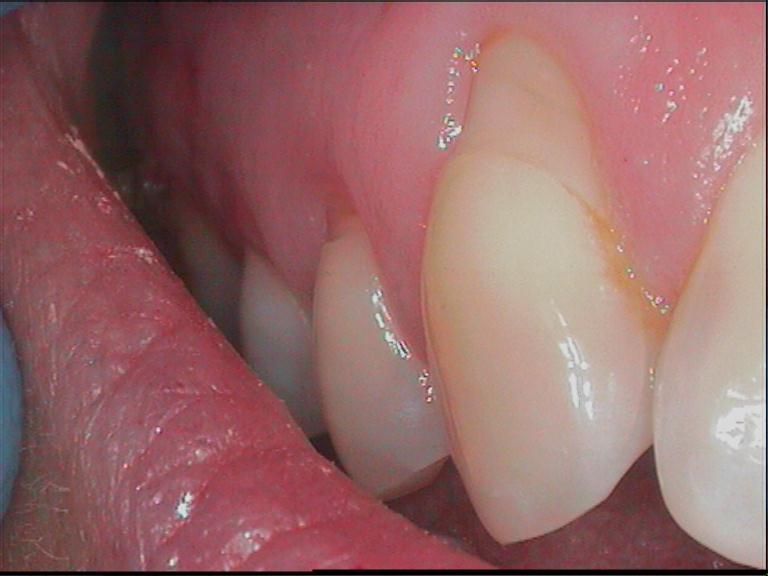

Premier signal d'alerte d'une parodontite naissante

Brosse électrique, hydropulseur, fil… sans résultat durable

Une fois perdues, elles ne reviennent jamais